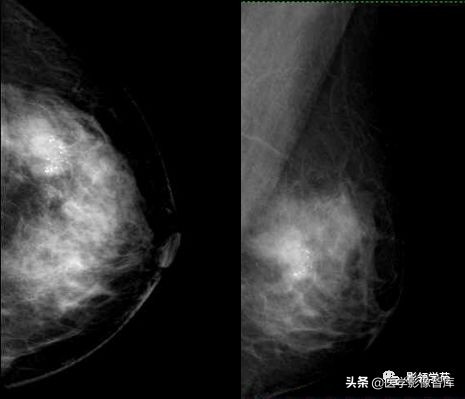

浸润性导管癌,多形性钙化、线虫状、分支杆状钙化。

女,50岁,多簇状细小多形性钙化,右乳外上浸润性导管癌。

不规则肿物伴多形性钙化,浸润性导管癌